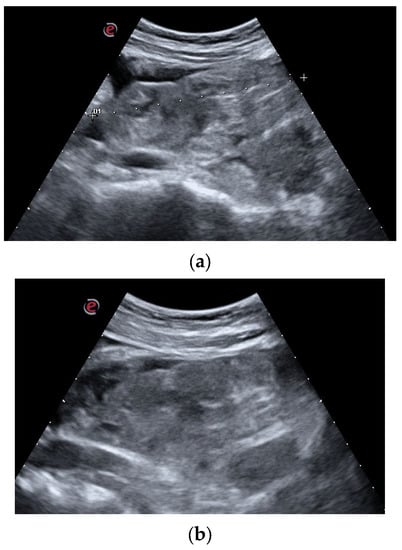

Under direct vision, the clot was progressively fragmented with the aid of the cystoscope, compressing the clot against the neobladder wall and weakening it. The vacuum effect of the 60 mL syringe permitted a progressive clot reduction into smaller fragments, which were progressively evacuated (Figure 3).

Intraoperative image: the evacuative approach is clearly shown. The 14 Ch urethral sheath is inserted into the Mitrofanoff. All operative channels are closed in this phase, while a 60 mL syringe is whipped at the optical access. The surgeon’s left hand firmly holds the sheath, while the right one (not visible in this picture) is dedicated to clot aspiration.

Due to the limited degrees of movement, in order to not damage the appendicovesicostomy, the contemporary US examination was performed till complete clot disruption was achieved (Figure 4a–d).

(a–d). Intraoperative US evaluation: the intraoperative US examination improved the assessment of the progressive clot disruption till its complete disappearance. In image (a), the main clot components are clearly visible. During the successive phases, images (b,c), clot dimensions progressively decrease, while a corpuscular suspension occupies the filling liquid. Finally, image (d), the clot is no more visible and only small fragments float in the lumen.